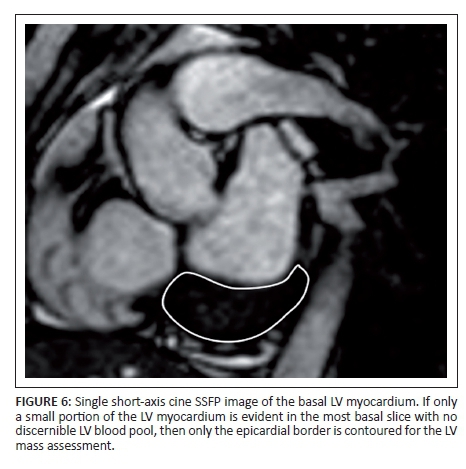

When contouring the endocardial border, the LV outflow tract should be included in the blood pool to the level of the aortic valve (Figure 5). If only myocardium is present in the most basal or most apical slice with no discernible LV blood pool, only an epicardial border is contoured for LV mass assessment (Figure 6). The papillary muscles are not part of the blood pool but, because most entry-level software does not automatically exclude the papillary muscles, and manual contouring of the papillary muscles is extremely labour intensive, the Task Force recommends that the papillary muscles be included or excluded at the operator's preference. Whether including or excluding the papillary muscles, that decision should be reflected in the report and should be consistently applied at any one institution.